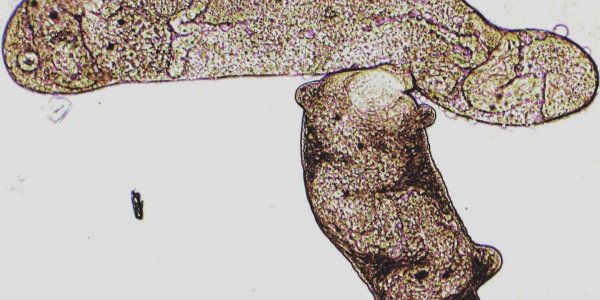

Non-Genetic Cancer Mechanism Found

Cancer can be caused solely by protein imbalances within cells, a study of ovarian cancer has found. The discovery is a major breakthrough because genetic aberrations have been seen as the main cause…